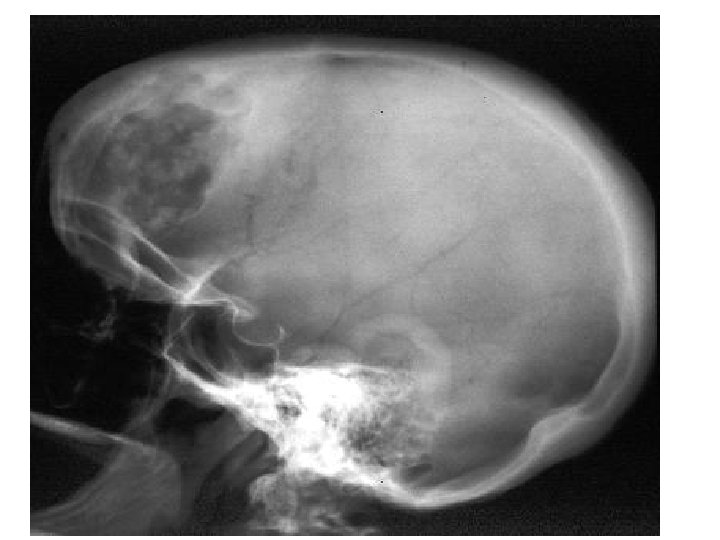

The Skull • 8 sutured bones in cranium • Facial bones: 13 sutured bones 1 mandible Cranium encases brain attachments for muscles sinuses

Bones of the Skull Figure 5. 11 Copyright © 2003 Pearson Education, Inc. publishing as Benjamin Cummings

Allows for growth